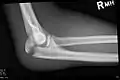

كسر الناتئ الزُجّي.